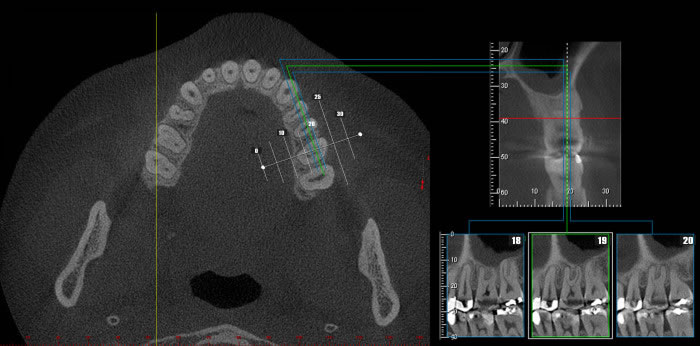

INTERPRETAÇÃO DA TOMOGRAFIA

Na apresentação básica, a reconstrução do exame tomográfico aparece como fatias de imagens

nos três planos: coronal, axial e sagital.

O radiologista “navega” por estas imagens, analisando toda a aquisição e com o auxílio de ferramentas ele monta e escolhe as imagens que irão compor o filme.

Nos softwares há ferramentas que permitem a reconstrução e a obtenção de novos cortes que mostram imagens de uso pontual na odontologia como os cortes transversais e longitudinais.

Os cortes transversais são cortes perpendiculares ao arco da maxila e mandíbula.

Na reconstrução panorâmica aparece uma régua no limite inferior que serve de localização para os cortes transversais.

Os cortes longitudinais são cortes no sentido vestíbulo lingual ou palatino, perpendiculares a uma reta traçada sobre o dente ou a área em questão.

1- A reconstrução panorâmica nada mais é que a representação em forma de panorâmica a partir de um arco criado sobre o rebordo, dessa forma, estruturas fora desses limites de reconstrução não aparecerão, diferente da radiografia panorâmica, onde estruturas “fora do foco” aparecem superpostas e por vezes borradas.

2- Nos cortes sagitais o perfil não muda para lado direito e esquerdo, os cortes são seqüenciais.

3- Por vezes utilizaremos a apresentação das imagens em MIP (Projeção de Intensidade Máxima) que dá o aspecto 3D de crânio seco.